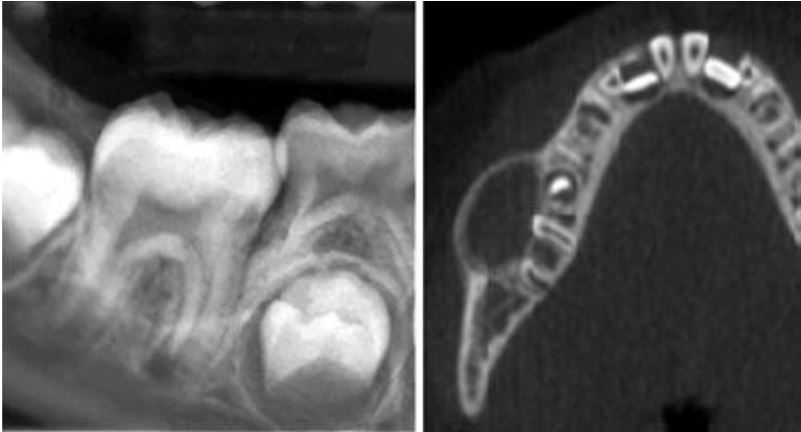

Răng sinh đôi (gemination)

Xảy ra khi một mầm răng có khuynh hướng chia thành 2 răng, nhưng sự phân chia này không hoàn toàn.

Tỉ lệ gặp ở răng sữa cao gấp 5 lần so với răng vĩnh viễn. Răng hay gặp nhất là răng cửa sữa hàm dưới và răng cửa vĩnh viễn hàm trên, bị một bên nhiều hơn hai bên.

Răng sinh đôi cũng hay có rãnh dọc theo mặt ngoài hoặc mặt trong, khía ở rìa cắn. Trên lâm sàng rất khó chẩn đoán phân biệt giữa răng dung hợp với răng sinh đôi.

Trên phim thì thấy răng sinh đôi chỉ có một buồng tủy rất rộng, chân răng to, thân răng chẻ đôi. Tuy vậy vẫn còn nhiều biến thể khác.